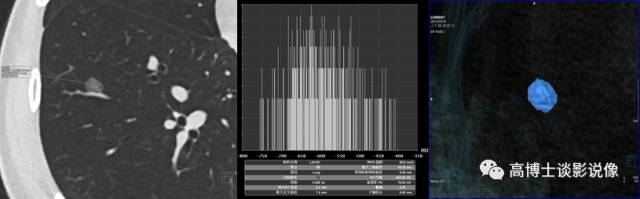

四、肺结节VRT重建

对于肺磨玻璃密度结节,VR重建直观显示结节形态、大小及结节内结构情况,结节的详细数据便于以后随访过程中发现细微动态变化情况。